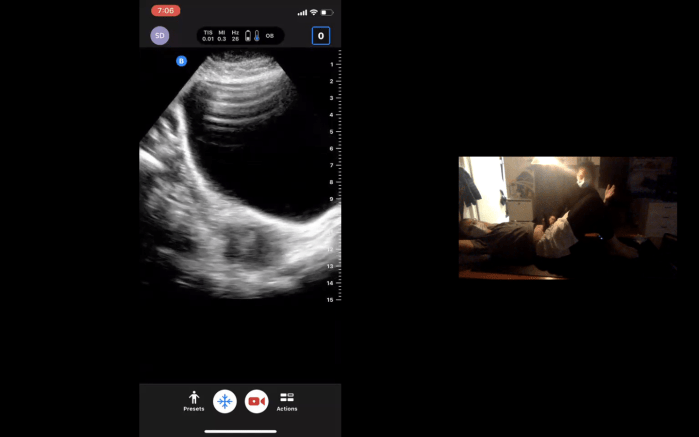

Thanks to our generous donors, we were able to achieve our 500$ milestone! As promised, here is an introduction to advanced cardiac views using our butterflyIQ ultrasound probes, made possible through last year’s campaign! https://www.youtube.com/watch?v=gXrXnPdxJXU&feature=youtu.be&ab_channel=McGillSeedsofChange